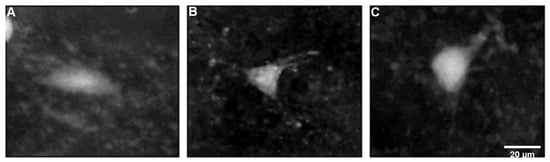

2.3. Characteristics of FJB-Positive Neurons